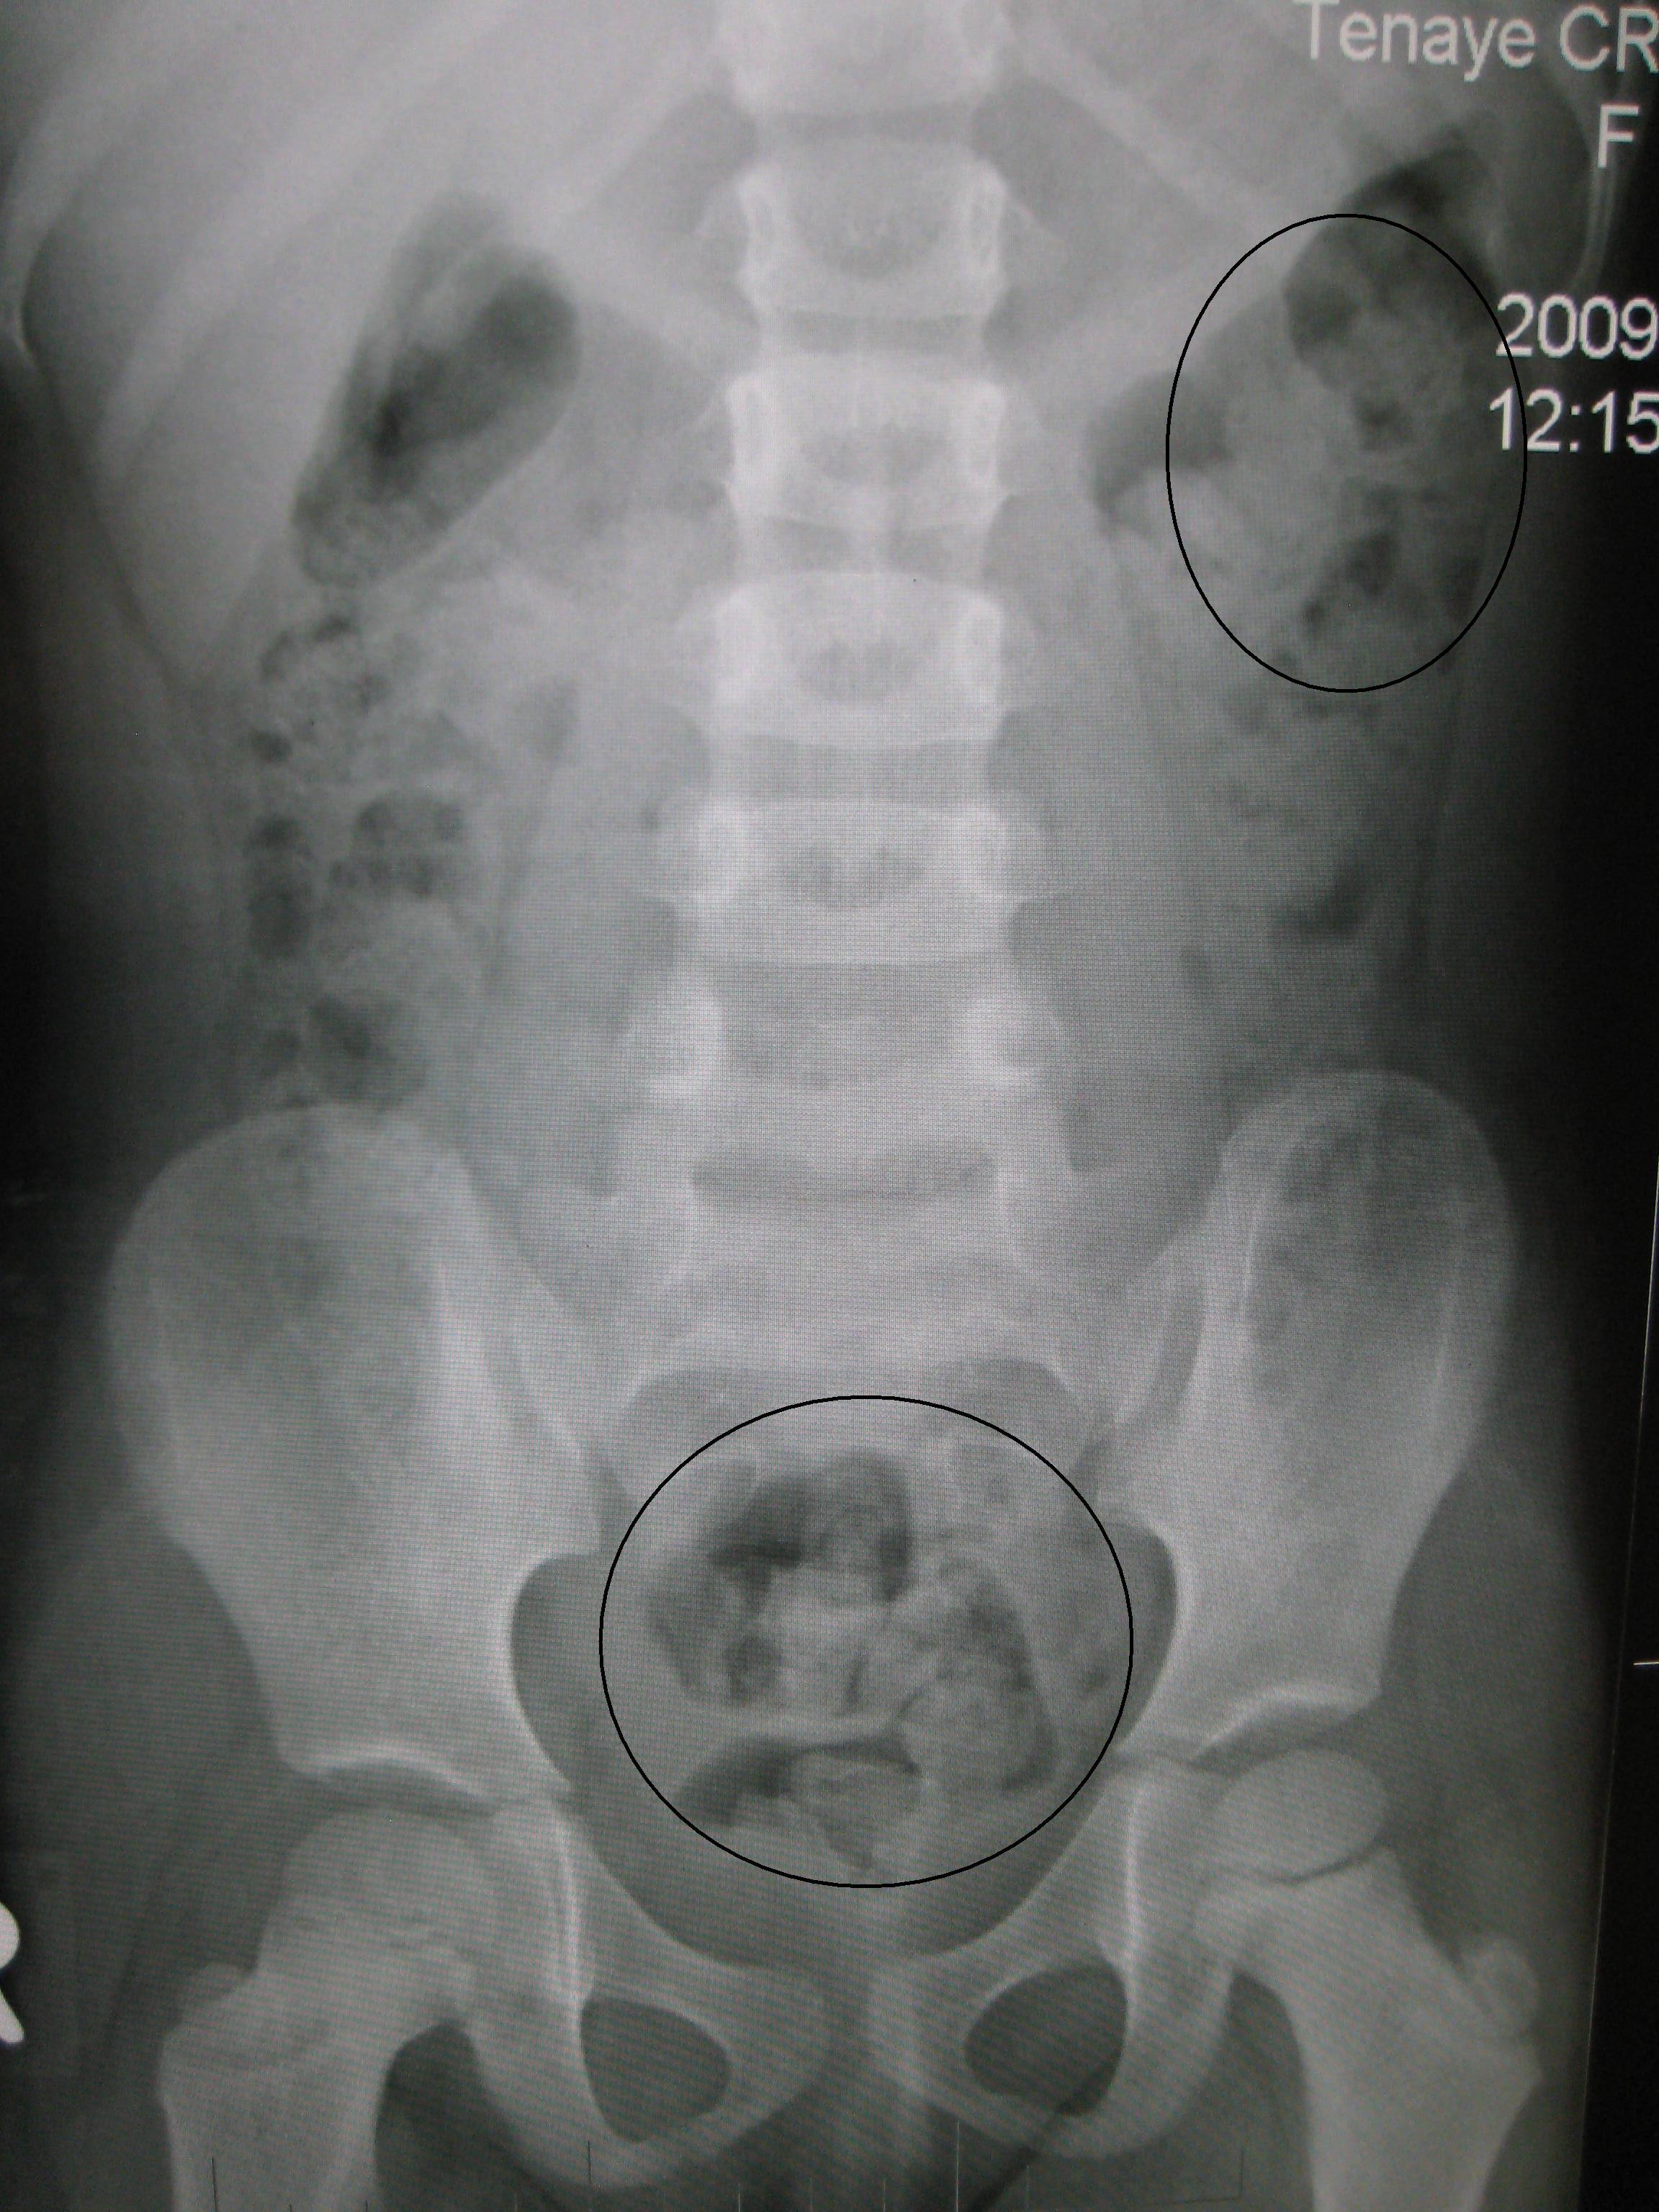

Different patients have different perceptions of symptoms. Web constipation is a condition in which a person has uncomfortable or infrequent bowel movements. Constipation is a problem with passing stool.

Most people think constipation means not having frequent enough bowel movements. Web chronic constipation is a polysymptomatic heterogeneous disorder. It can also cause pain, bloating, nausea, and other symptoms.

Constipation is difficult or infrequent passage of stool, hardness of stool, or a feeling of incomplete evacuation. But other medical conditions or certain medicines. A condition which makes someone unable to empty their bowels as often as they should: